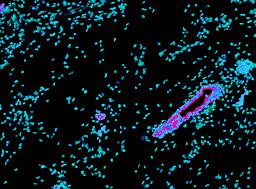

Pancreatic ductal adenocarcinoma is a lethal disease with limited treatment options and poor survival. We studied 83 spatial samples from 31 patients (11 treatment-naïve and 20 treated) using single-cell/nucleus RNA sequencing, bulk-proteogenomics, spatial transcriptomics and cellular imaging. Subpopulations of tumor cells exhibited signatures of proliferation, KRAS signaling, cell stress and epithelial-to-mesenchymal transition. Mapping mutations and copy number events distinguished tumor populations from normal and transitional cells, including acinar-to-ductal metaplasia and pancreatic intraepithelial neoplasia. Pathology-assisted deconvolution of spatial transcriptomic data identified tumor and transitional subpopulations with distinct histological features. We showed coordinated expression of TIGIT in exhausted and regulatory T cells and Nectin in tumor cells. Chemo-resistant samples contain a threefold enrichment of inflammatory cancer-associated fibroblasts that upregulate metallothioneins. Our study reveals a deeper understanding of the intricate substructure of pancreatic ductal adenocarcinoma tumors that could help improve therapy for patients with this disease.